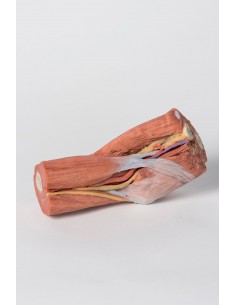

3D Anatomy 1.0 - Extremidades superiores

Ligamentos del miembro superior - Erler Zimmer 3D anatomy Series MP1520